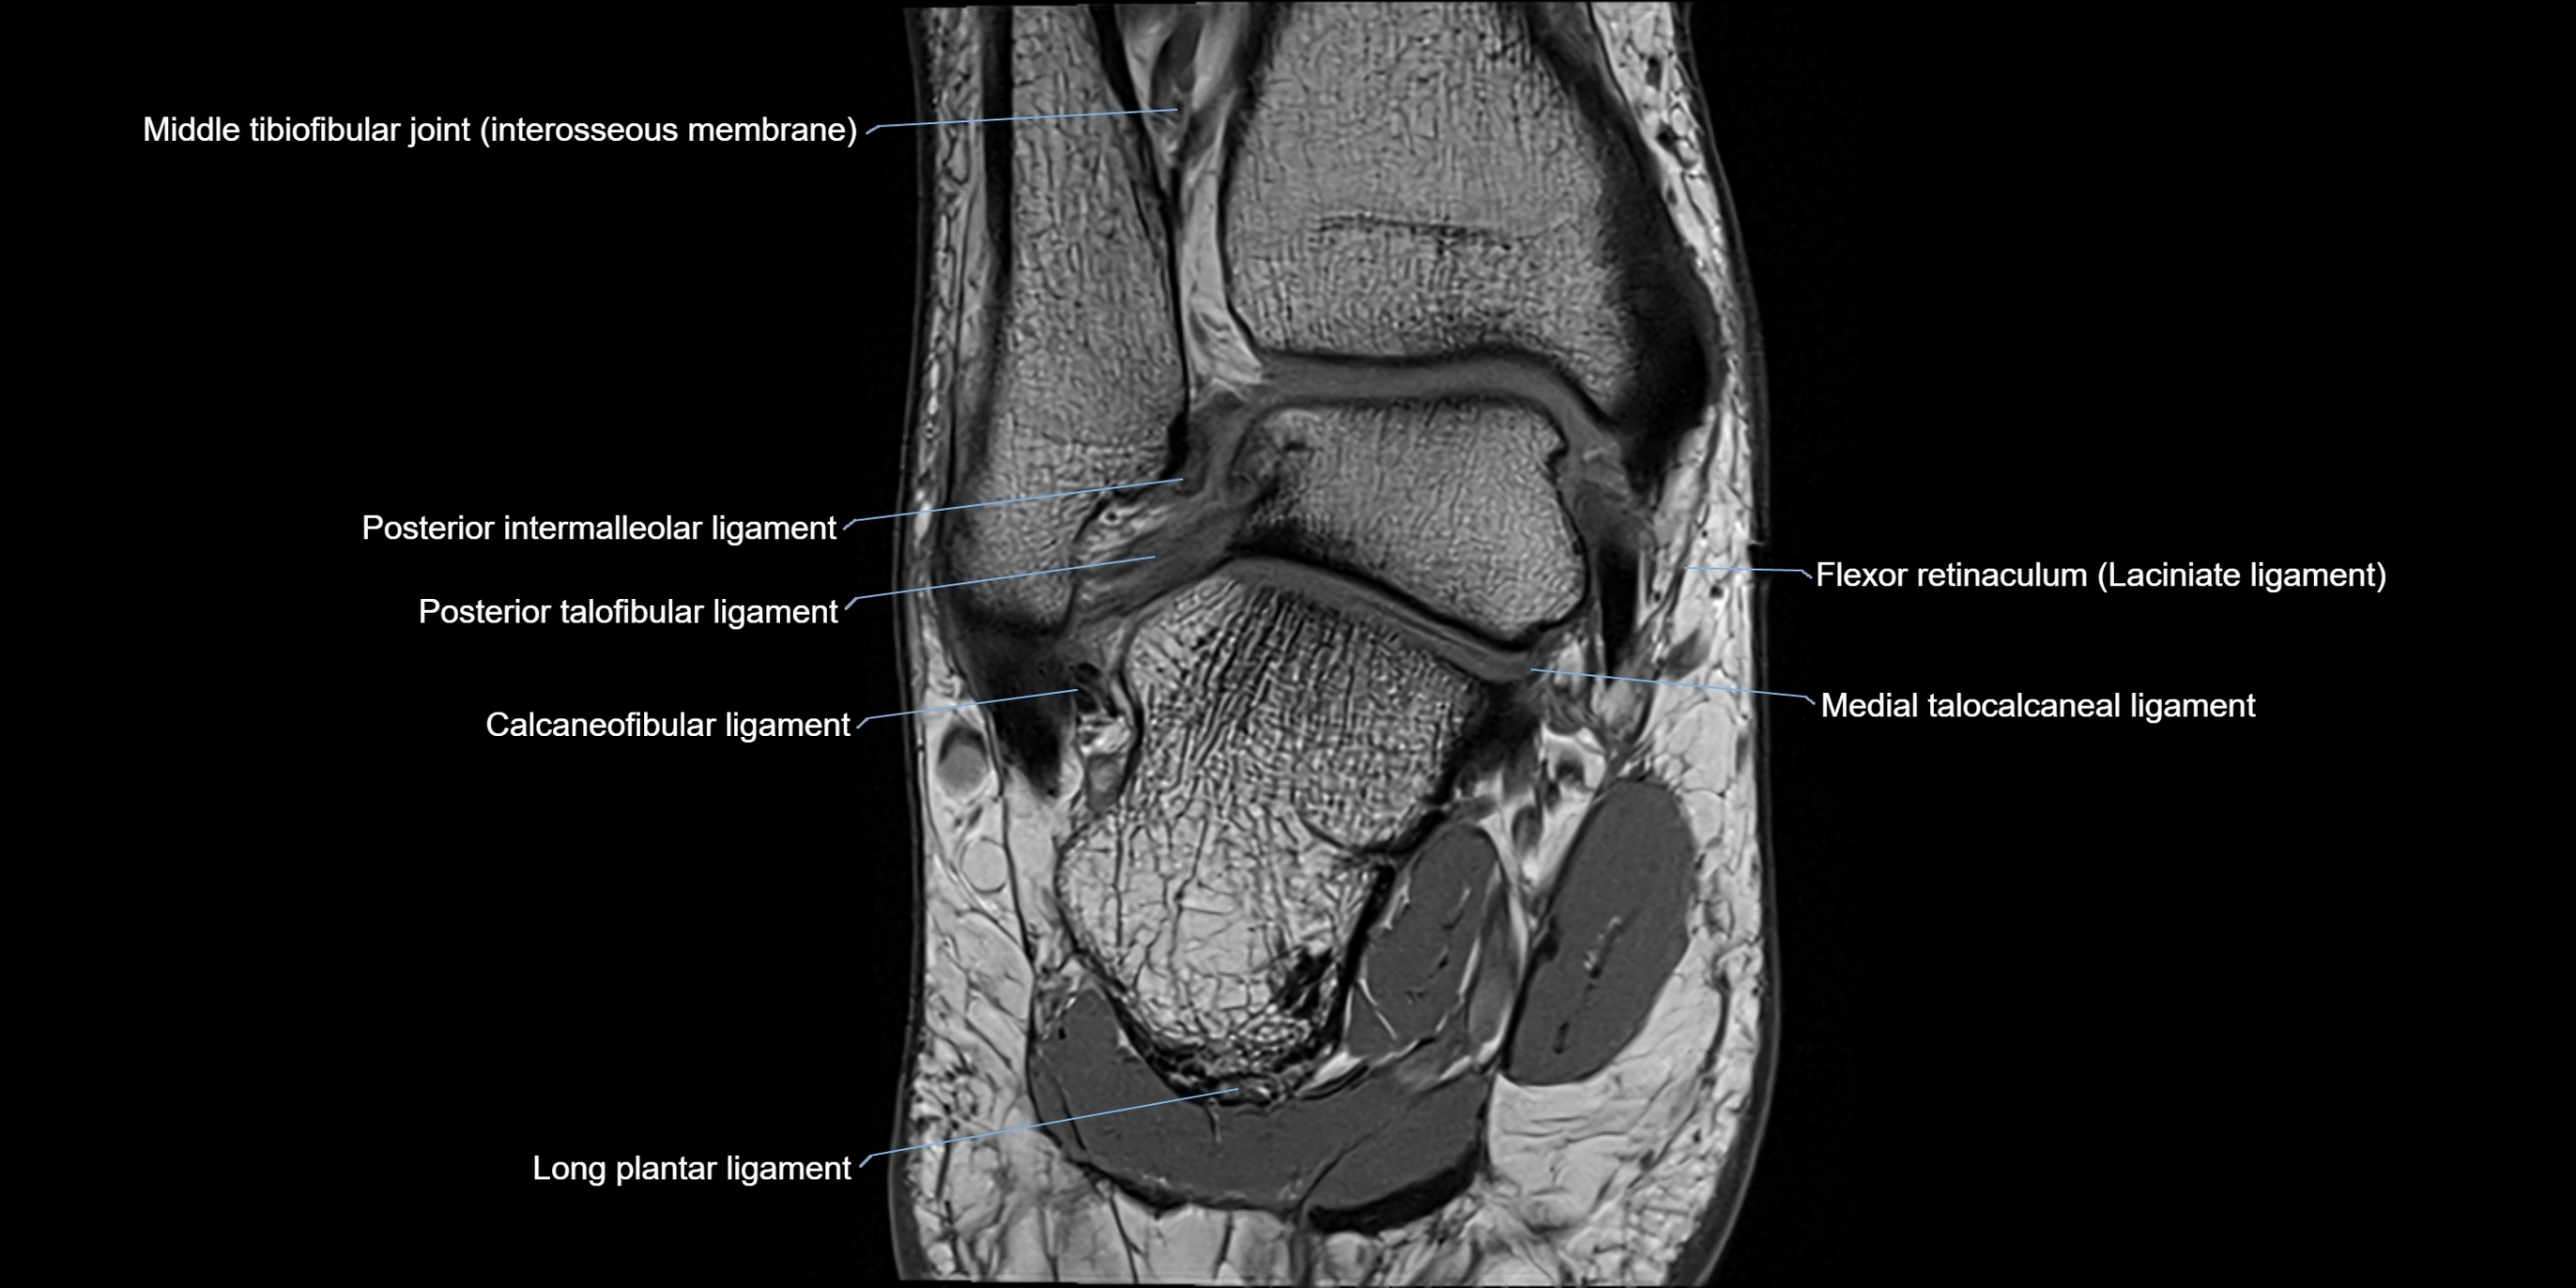

MRI image

image